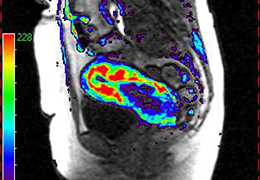

View X-Ray CT & MRI Scans Fast and Easily

Designed for surgeons, Pro Surgical 3D makes it easy to view patient scans quickly. Pro Surgical 3D facilitates the optimal 3D treatment and assessment workflows based on X-ray CT and MRI scans – and best of all, it’s FREE!

Designed mainly for CT and MR DICOM modalities.

Performs 3D reconstruction and volume rendering.

Oblique slicing.